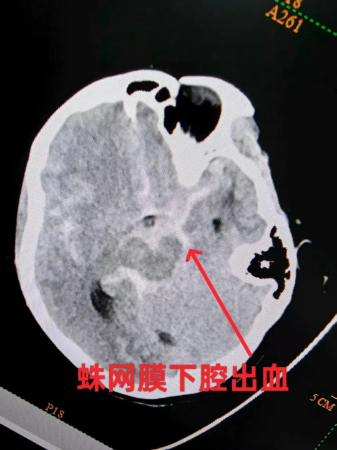

患者颅脑CT显示:患者大量蛛网膜下腔出血、脑挫裂伤、多处骨折,急诊造影:左侧后交通动脉瘤,瘤体上发出后交通动脉。